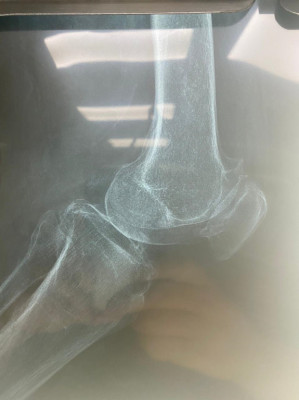

Prótesis total de rodilla

Envíado por Dr. José Israel Flores Hernández